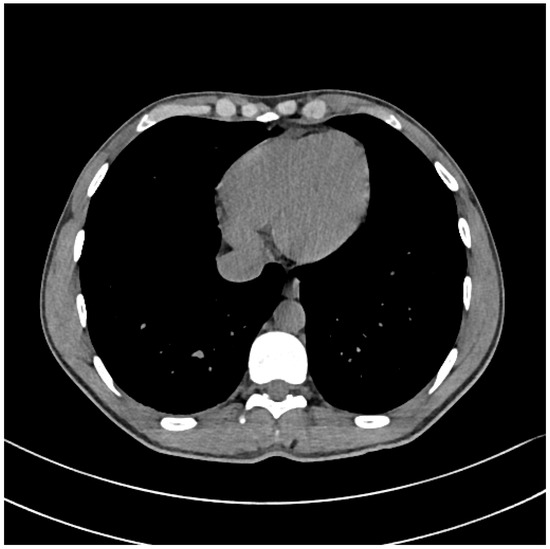

After considering the risk/benefit ratio in the case and excluding any existing apparent absolute contraindications to a Hyperbaric Oxygen (HBO) exposure (i.e., bullous lung disease, concurrent undrained Pneumothorax), we made the patient undergo a slightly modified US Navy Treatment Table 6 (USN TT6.1) (Available at: https://www.uhms.org/images/DCS-and-AGE-Journal-Watch/recompression_therapy_usn_di.pdf, accessed on 28 November 2022, at page 55 of 142 and Chap/Para: 20–5 at Page: 20–13). This specific HBO protocol lasts almost 6 h and is considered the standard of care for these potentially life-threatening occurrences, resulting in a final complete restitution, at least for this air bubble lesion (Figure 2).

Figure 2.

Post-HBO: Chest CT scan w/o contrast medium.